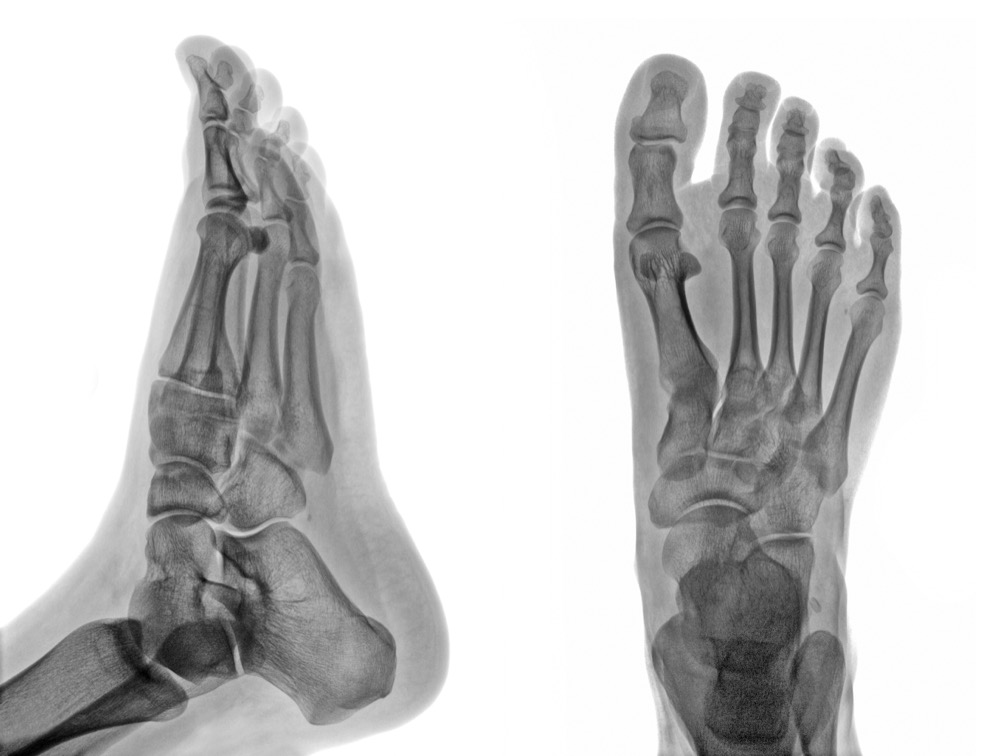

On-site digital x-ray imaging for fast, accurate diagnosis.

Our on-site digital x-ray system provides immediate, high-resolution images of bones and joints in the foot and ankle. Digital imaging offers lower radiation exposure than traditional x-rays, and results are available in minutes — allowing Dr. Quach to diagnose fractures, arthritis, deformities, and other conditions during your visit.

Having digital x-ray capability on-site is a significant advantage for our patients. Rather than scheduling imaging at a separate facility and waiting for results, we can take and analyze x-rays during your appointment — allowing Dr. Quach to diagnose conditions and begin treatment in a single visit. Our McAllen office is equipped with digital radiography.

Digital x-rays are used to diagnose a wide range of foot and ankle conditions including fractures, stress fractures, arthritis, bone spurs, joint dislocations, bunion and hammer toe deformities, and foreign bodies. They are also essential for pre-surgical planning and post-operative follow-up to monitor bone healing and hardware placement.